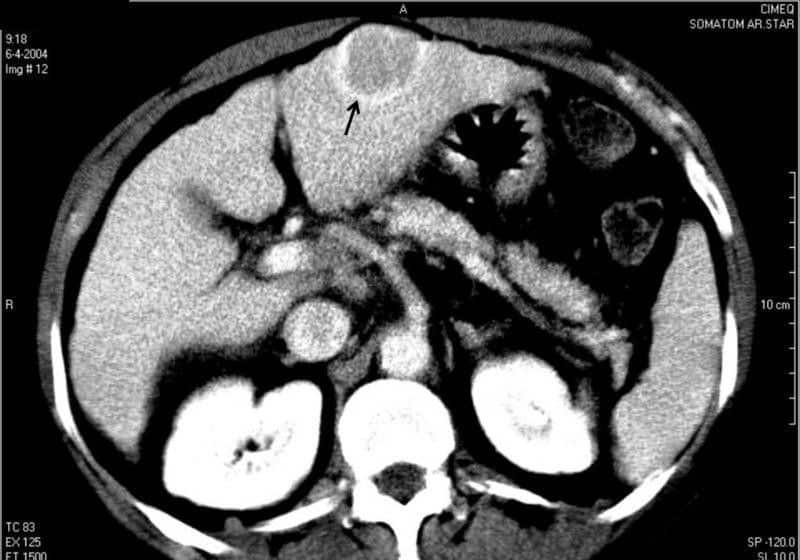

La presencia de lesiones focales múltiples en el hígado sugiere una naturaleza metastásica. Sus orígenes más frecuentes son el colon, el estómago, el pulmón, la mama, los riñones y el útero, variando su morfología y vascularización según el tipo de metástasis. Por ello, hay que efectuar una exploración helicoidal con contraste tanto en fase venosa como en fase arterial precoz, y así poder definir adecuadamente las lesiones más pequeñas sin confusión posible de las venas suprahepáticas con metástasis.

Las metástasis hepáticas suelen distinguirse de los quistes benignos por su mala delimitación y su realce tras el medio de contraste.

Fig. TC de la parte superior del abdomen de un paciente con carcinoma del intestino grueso que muestra metástasis múltiple hacia el hígado.